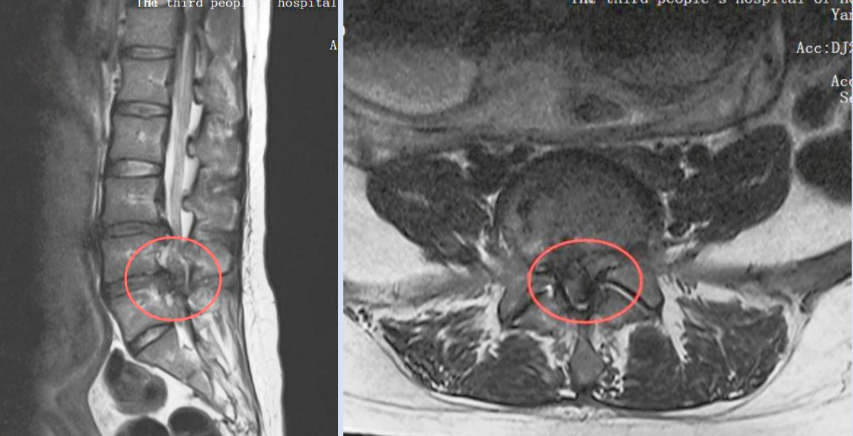

当地医院诊断后,结果令全家心弦紧绷——这不是普通的孕期不适,而是由严重腰椎间盘突出引发的“马尾神经综合征”

这是一种急症,若不及时处理,可能导致永久性的下肢瘫痪、大小便功能障碍。更棘手的是,李女士还怀着宝宝。